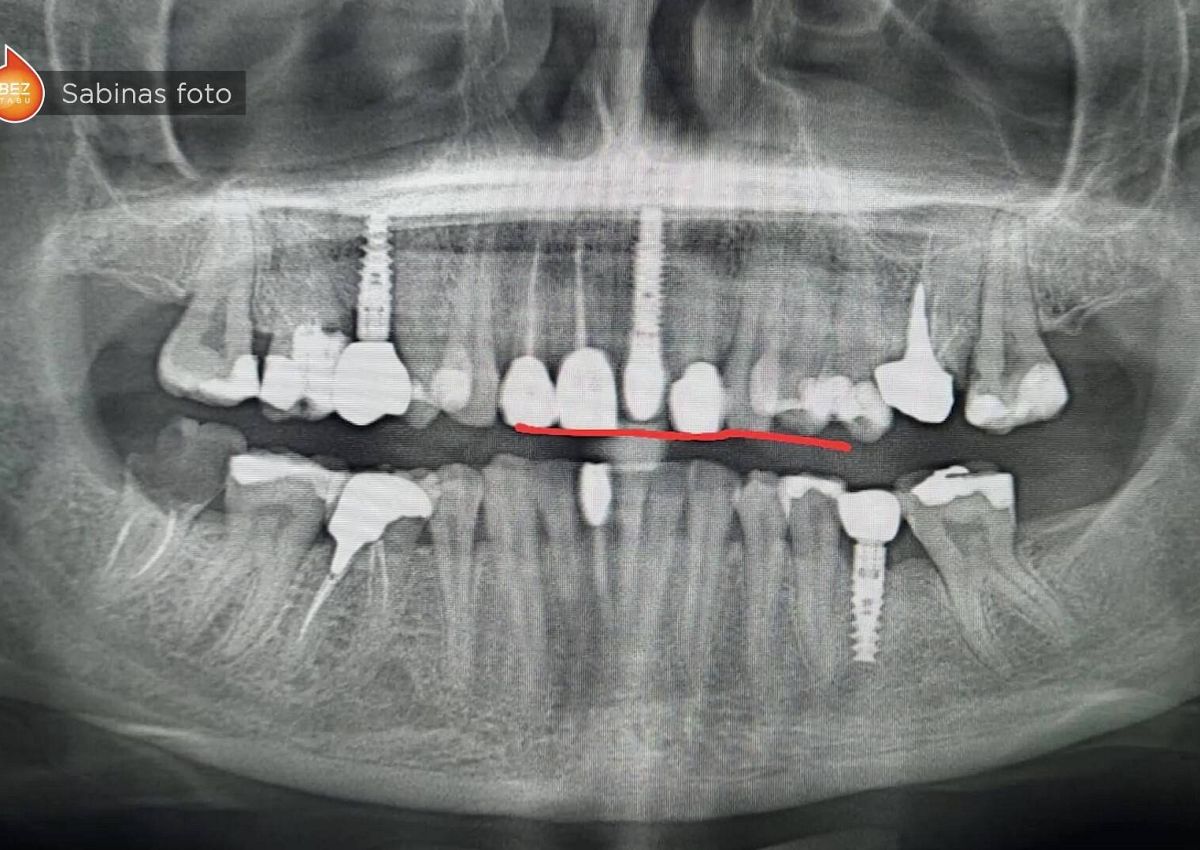

"Pašlaik doma vien par nepieciešamību saņemt zobārstniecības pakalpojumus biedē. Zinot pakalpojumu cenas, iedzīvotāji gadiem ilgi atliek zobārsta apmeklējumu. Tas situācijas pasliktina un veicina ar zobu veselību saistīto problēmu attīstību līdz pat antibiotiku lietošanai un zobu zaudēšanai, kas arī nebūt nav bezmaksas process," skaidro Ūdris.